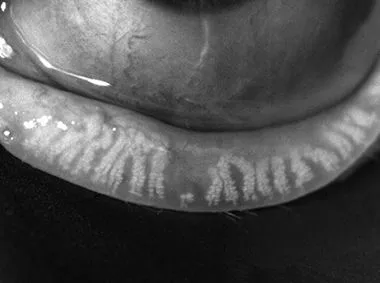

Dynamic Meibomian Imaging

MEIBOMIAN GLANDS IN HIGH DEFINITION1

Dynamic Illumination

Surface lighting originates from multiple light sources to minimize reflection.

Adaptive Transillumination

Changes to the light intensity across the surface of the illuminator compensate for the lid thickness variations between patients.

Dual-Mode DMI

Dynamic Illumination offers an enhanced view of meibomian gland structure.

Dynamic Meibomian Gland Imaging

Utilizes advanced illumination technology to capture high-definition images.